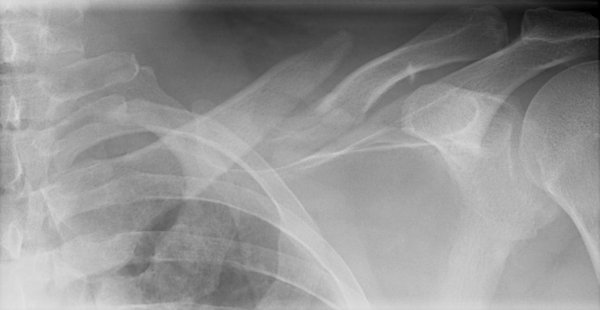

Return to Clavicle Fracture